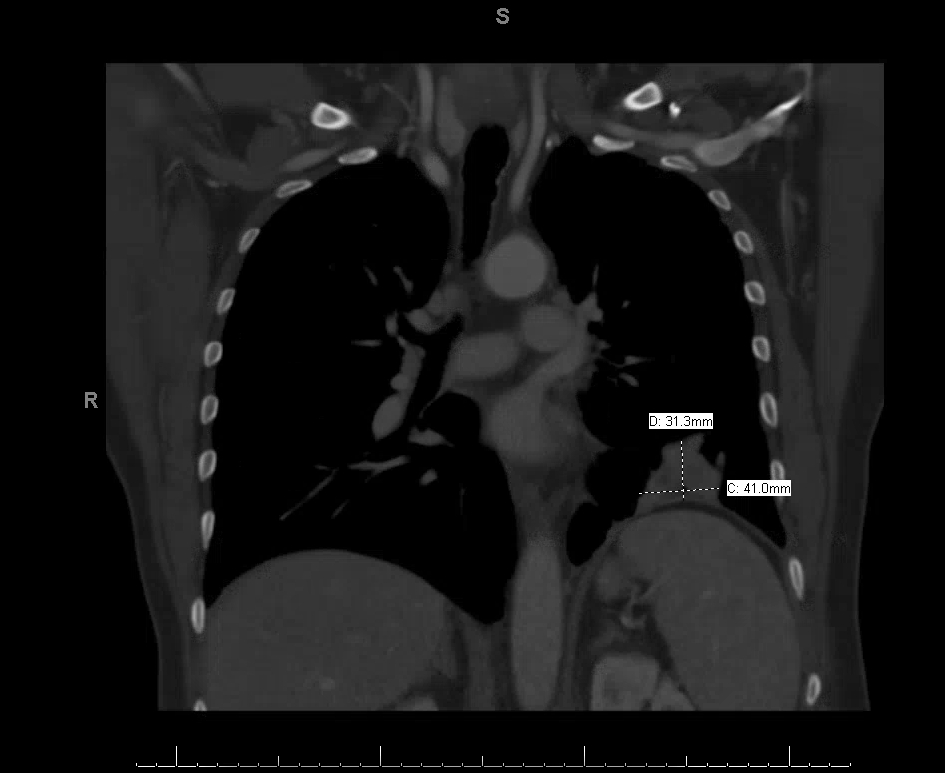

CT chest with contrast showed a large left pleural effusion with total collapse of the left lower lobe, as well as a right kidney lesion. Subsequent imaging demonstrated a left lower lobe mass (3.4 cm) with numerous left-sided pleural-based nodules and one pleural-based mass (4.1 cm), with imaging characteristics concerning for metastatic disease (Figure 1). CT abdomen and pelvis with contrast showed a solid hyperdense mass in the mid pole of the right kidney (Figure 2). PET scan showed numerous hypermetabolic left pulmonary nodules, most consistent with pleural metastasis, including diffuse hypermetabolic pleural thickening throughout the left hemithorax and multiple hypermetabolic pleural-based nodules. PET scan also showed a solid right renal lesion (2.8 cm) with low-grade FDG uptake most suggestive of renal cell carcinoma.